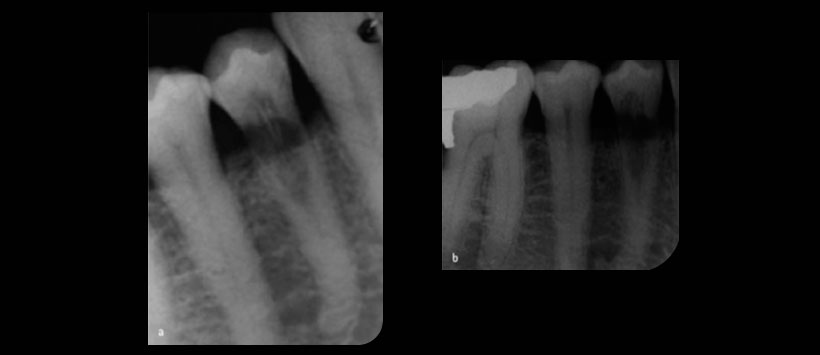

Si se sospecha una reabsorción, se deben tomar una o más radiografías periapicales. Se deben considerar las radiografías adquiridas mediante la técnica paralela, ya que esta técnica proporcionará más información sobre el sitio y el tipo de lesión. Las lesiones internas, sin embargo, deben permanecer en una posición similar en relación con el conducto radicular. Las limitaciones de la radiografía dental de rutina son ampliamente conocidas. Superposición de las características anatómicas, distorsión inadvertida cuando se usan soportes de película y la naturaleza bidimensional de la imagen puede dar como resultado una imagen menos que ideal. (Figura 1) Además, se ha demostrado que las radiografías pueden no ser lo suficientemente sensibles como para permitir el diagnóstico de lesiones de resorción externas. Se ha demostrado que el tamaño de la lesión, su ubicación, su anatomía local y su densidad ósea influyen en la detección de lesiones.

Las cavidades de reabsorción pequeñas y aquellas presentes en las superficies bucal y lingual tienen más probabilidades de permanecer sin diagnosticar. Se han demostrado diferencias significativas en la detección de reabsorción inter e intra. Por lo tanto, los médicos deberían tenga en cuenta estas limitaciones, examine las radiografías en las condiciones adecuadas y solicite una opinión para obtener más imágenes en caso de duda.